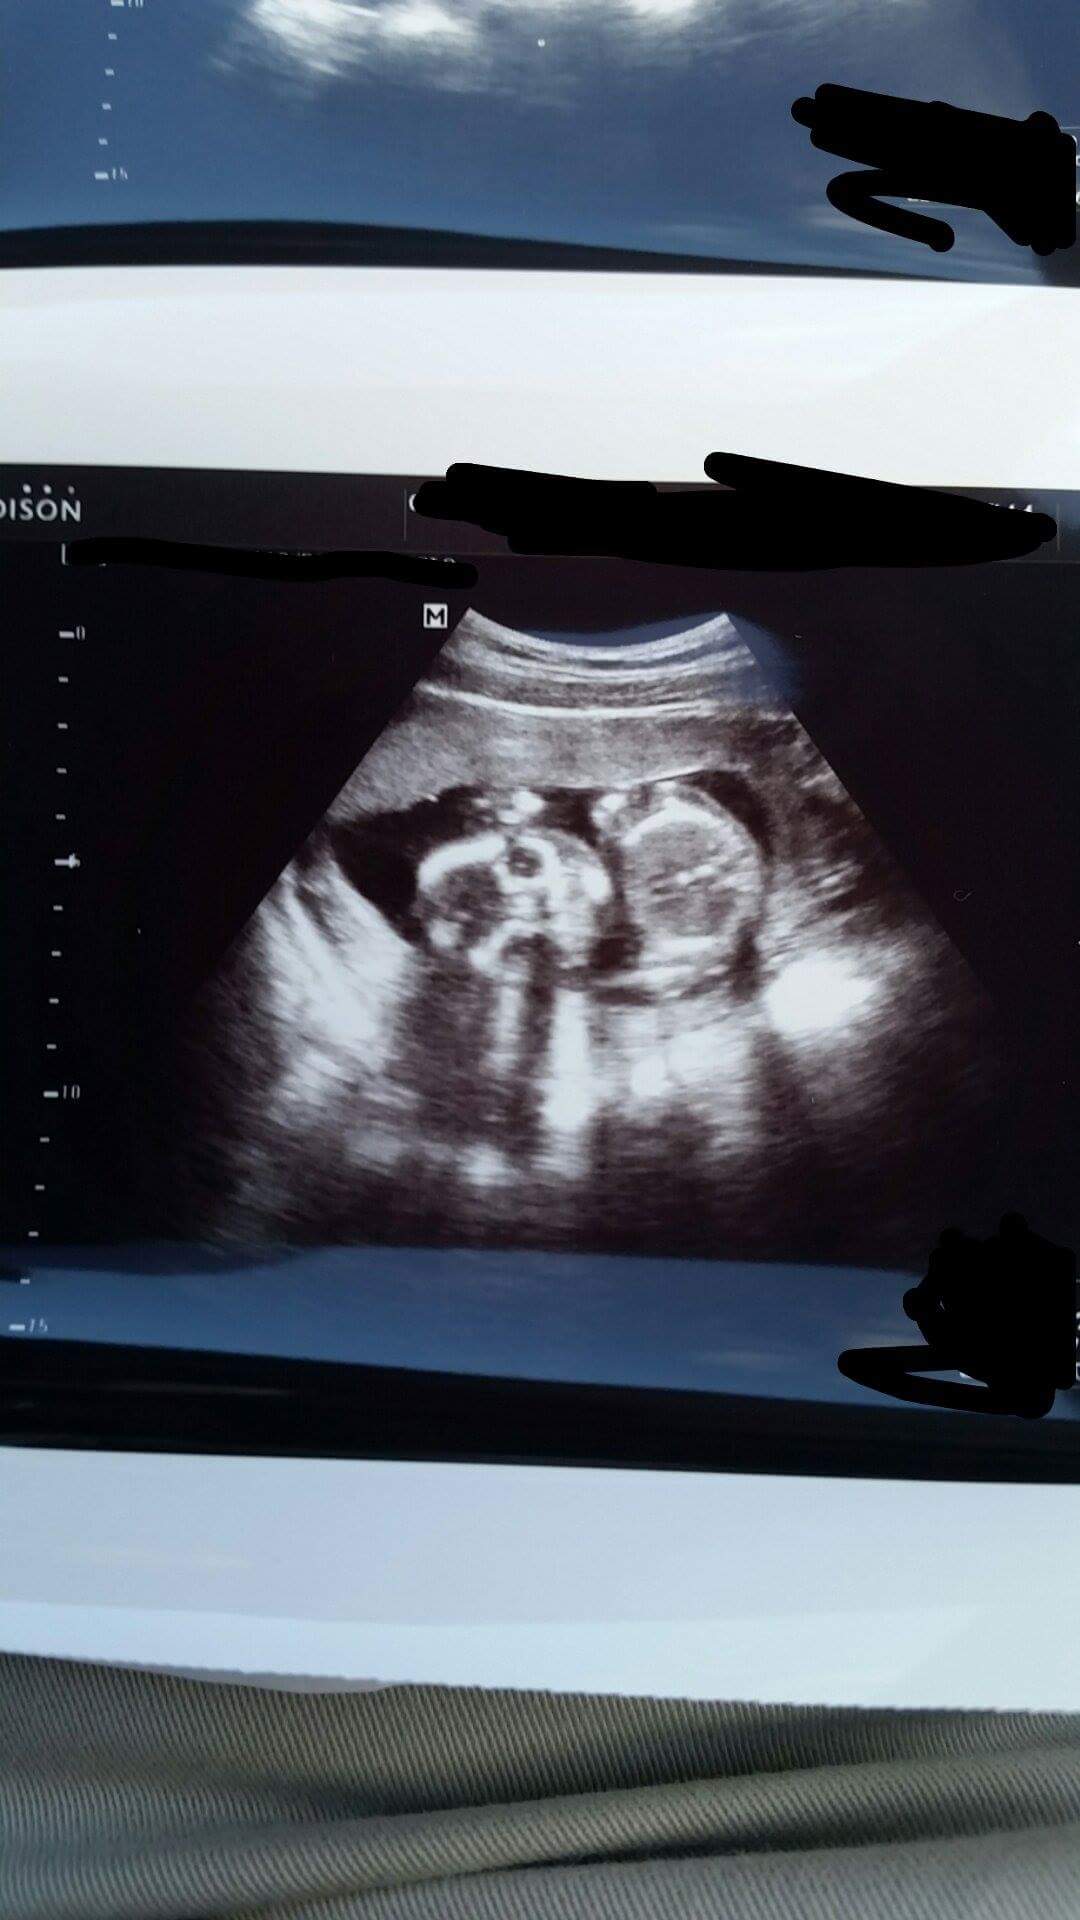

13w5d in the photo